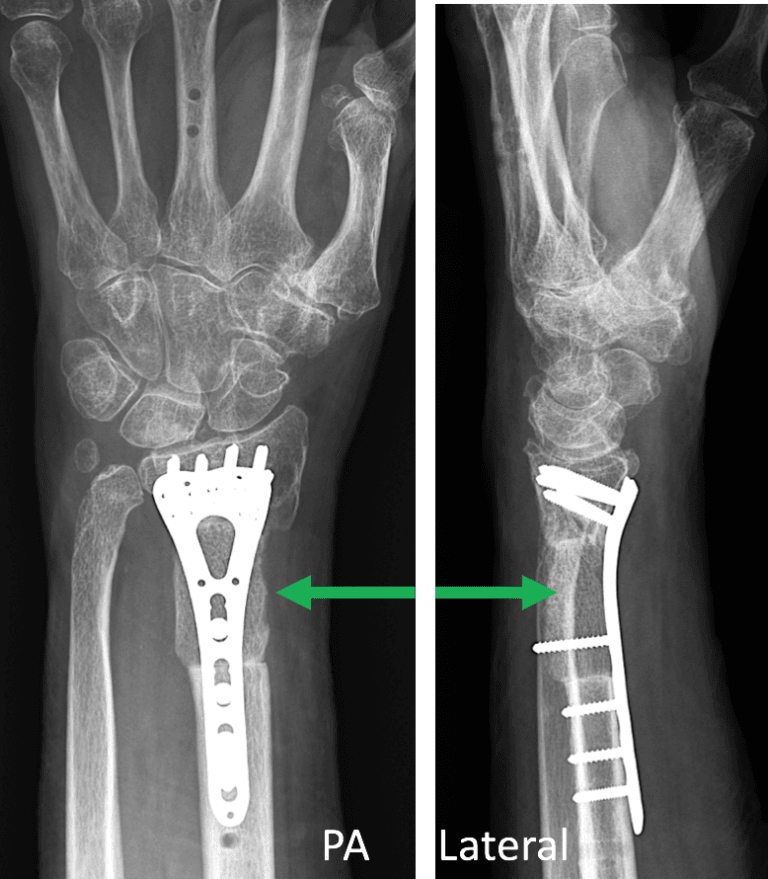

Complex open ulna & radius fracture. 2 months, 2 plates, 16 screws Radius Bone Graft Pedicled grafts from the distal radius, medial femoral condyle, ribs, and fibula have improved outcomes in challenging. Bone graft helps to maintain the surgical corrections but with possible donor. Distal radius malunion is the most common complication of distal radius fractures. Prevention of malunion of a distal radius fracture is the best course of action. Diagnosis is made with orthogonal. Radius Bone Graft.

Orthogonal Plate Fixation With Corrective Osteotomy for Treatment of Radius Bone Graft Diagnosis is made with orthogonal radiographs of the wrist demonstrating decreased. Surgical treatment of fractures of the distal radius can involve the implantation of bone scaffolding materials (bone grafts and. Distal radius malunion is the most common complication of distal radius fractures. This article will review the biology of bone grafts and the clinical evidence in the use of bone. Radius Bone Graft.